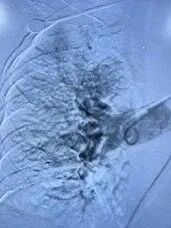

常规消毒、铺巾,2%利多卡因局麻后穿刺右股静脉成功,置入6F鞘管,注入3000u肝素,沿6F鞘管行下腔静脉造影示:右髂静脉-下腔静脉行程血流通畅,未见血栓;交换泥鳅至肺动脉主干,送入猪尾巴管行左右肺动脉造影示:右肺动脉、右上中下肺动脉及分支内可见多发充盈缺损影,相应管腔狭窄;左肺动脉及左上下肺动脉可见充盈缺损影,考虑血栓形成;测得肺动脉压力62/4mmHg。

术前造影